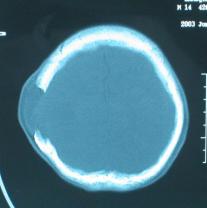

头颅CT和MRI可见颅骨缺损区下方软脑膜囊肿、脑软化灶或脑室穿通畸形(图2)。

图2:①和②CT及骨窗相显示右顶部颅骨缺损,其下方脑组织呈低密度改变;③-⑥MRI右顶局部颅骨缺如,脑组织轻度向外膨隆,右顶叶侧脑室体部旁局部脑组织缺如,代之以囊性长T1、长T2信号。